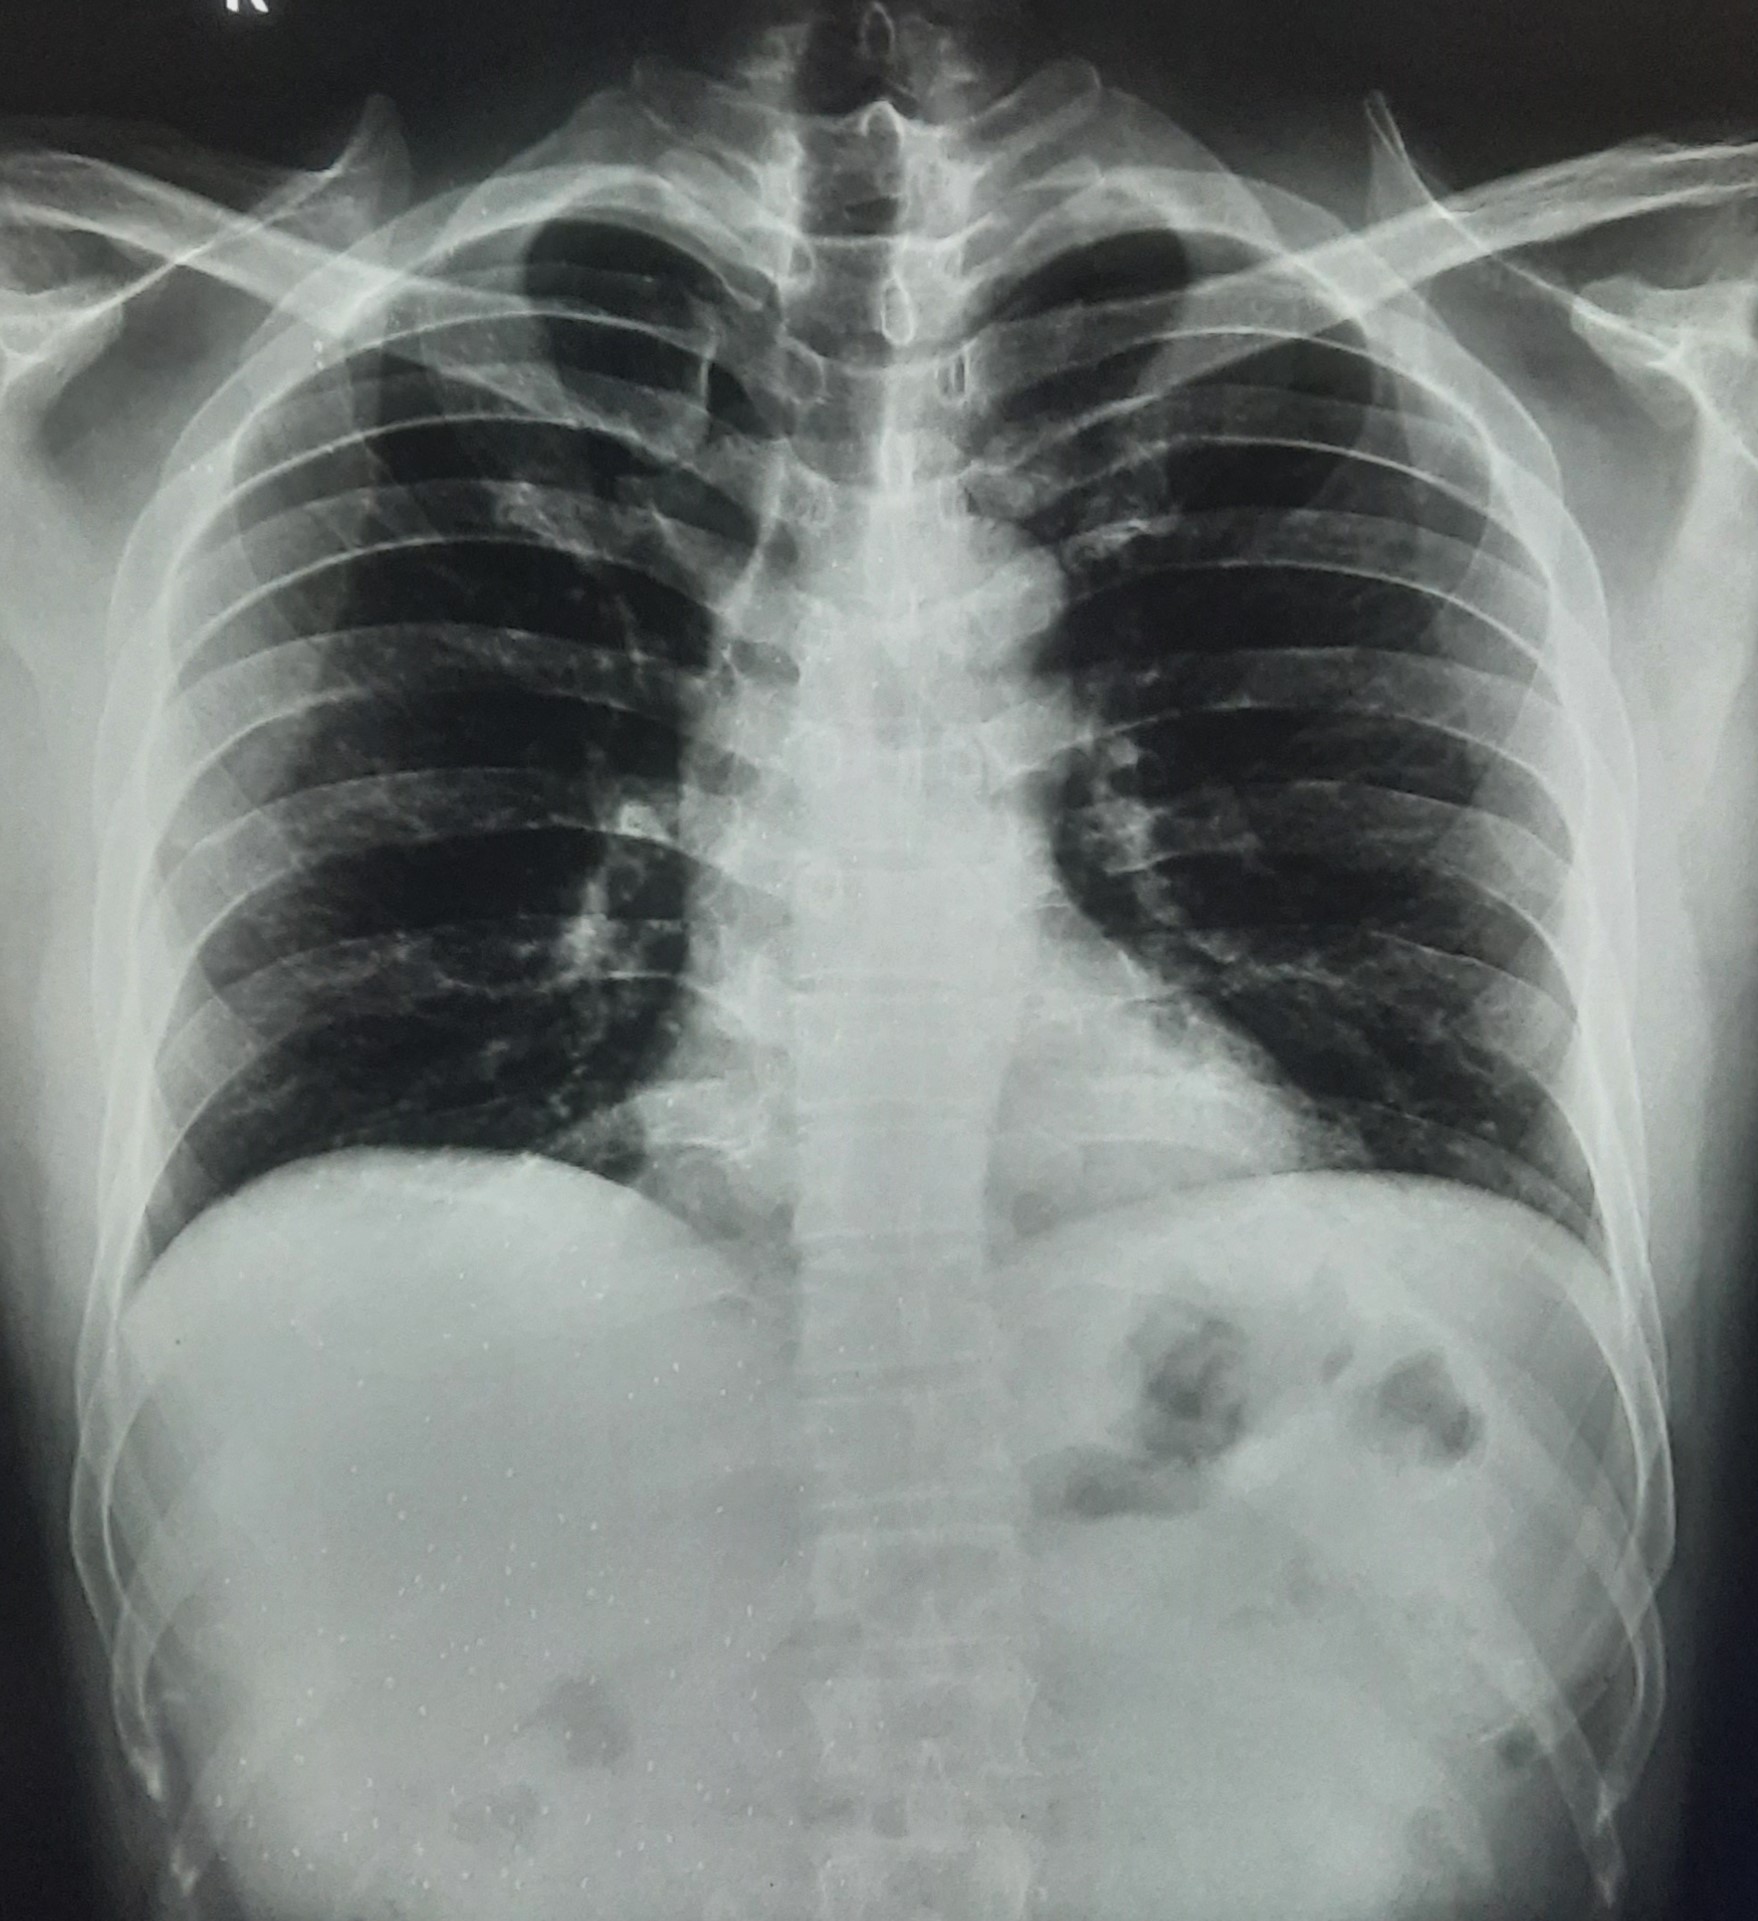

| 271 | IGGMC, Nagpur, Nagpur | P2 | 29-4201 | Abddul Qayyam | Consent taken on Paper | 75 Yrs. |

Provisional Diag : Upper Respiratory Tract Infection

Final Diag : FIBROSIS |

Non-TB Case (Confirmed) | RETICULAR OPACITIES NOTED IN PREDOMINANTLY IN UPPER ZONE OF RIGHT LUNG PARENCHYMA | Abnormality visible on x-ray |